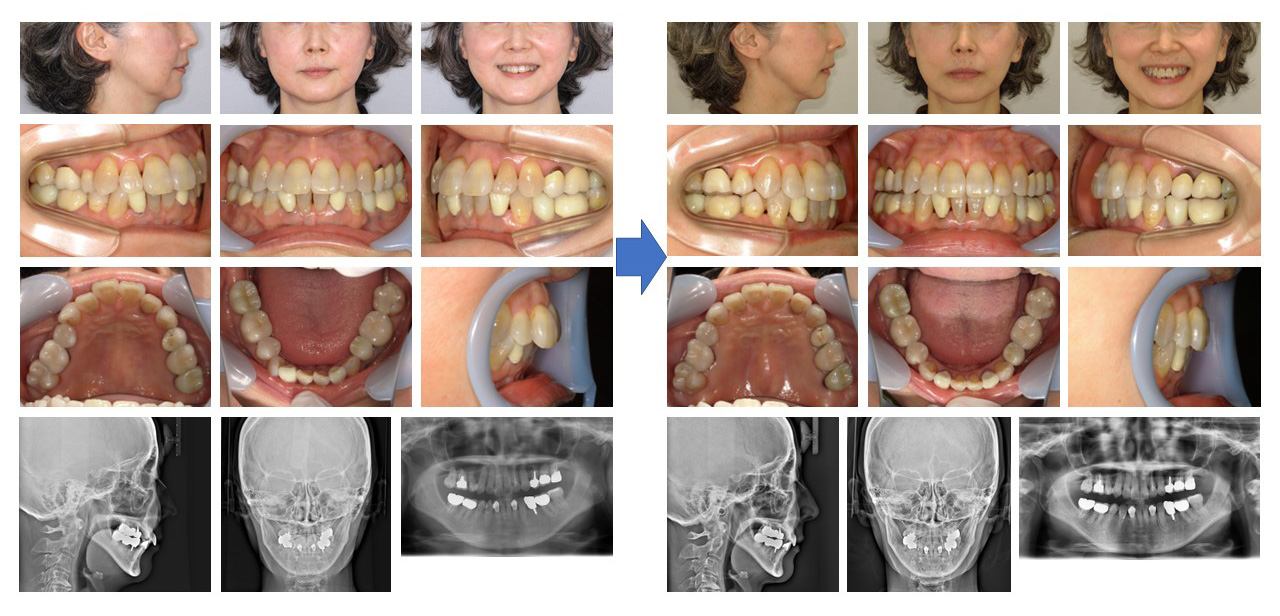

【治療例】初診時年齢:61歳0か月 / 性別:女性 / 主訴:上前歯が出てきた、下のガタガタ

治療の概要:45年前に名誉院長が上下顎両側第一小臼歯を抜歯をした症例であるが、上下顎前歯部に後戻り(叢生)が認められた。隣接歯面の削合を行いながらマウスピース型(アライナー型)矯正装置(インビザライン®)にて叢生の改善を行った。

主訴:上前歯が出てきた、下のガタガタ

診断名:上下顎両側第一小臼歯の既抜歯を行っていた後戻り症例

使用した主な装置:マウスピース型(アライナー型)矯正装置(インビザライン®)

抜歯/非抜歯および抜歯部位:非抜歯(上下顎両側第一小臼歯の既抜歯)

※こちらの症例は2022年6月から2023年11月に行った矯正です(現在も経過観察中)

治療期間:1年5か月

治療回数:22回

リスクの副作用:歯の移動や抜歯による違和感や疼痛、口内炎、歯肉退縮、歯根吸収が生じることがある